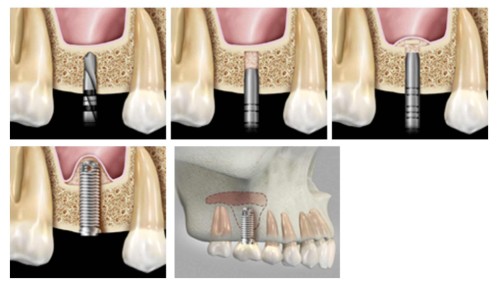

Bone grafting can repair implant sites with inadequate bone structure due to previous extractions, gum disease, or injuries. The bone is either obtained from a tissue bank or your own bone is taken from the jaw, hip or tibia (below the knee). Sinus bone grafts are also performed to replace bone in the posterior upper jaw. In addition, special membranes may be utilized that dissolve under the gum to protect the bone graft, as well as encourage bone regeneration. This is called guided bone regeneration, or guided tissue regeneration.

Major bone grafts are typically performed to repair defects of the jaws. These defects may arise as a result of traumatic injuries, tumor surgery, or congenital defects. Large defects are repaired using the patient’s own bone. This bone is harvested from a number of different areas depending on the size needed. The skull (cranium), hip (iliac crest), and lateral knee (tibia), are common donor sites. These procedures are routinely performed in an operating room and require a hospital stay. Contact our office for more information.

The key to a successful and long-lasting dental implant is the quality and quantity of jaw bone to which the implant will be attached. If bone loss has occurred due to injury or periodontal disease, a sinus augmentation can raise the sinus floor and allow for new bone formation. A sinus lift is one of the most common bone grafting procedures for patients with bone loss in the upper jaw. The procedure seeks to grow bone in the floor of the maxillary sinus above the bony ridge of the gum line that anchors the teeth in the upper jaw. This enables dental implants to be placed and secured in the new bone growth.

The inferior alveolar nerve, which gives feeling to the lower lip and chin, may need to be moved in order to make room for the placement of dental implants in the lower jaw. A nerve repositioning procedure is limited to the lower jaw and may be indicated when teeth are missing in the area of the two back molars and/or second premolars. This procedure is considered a very aggressive approach since there is almost always some postoperative numbness of the lower lip and jaw area, which typically dissipates very slowly, but may be permanent. Usually other, less aggressive options are considered first (placement of blade implants, etc).

Typically, we remove an outer section of the cheek on the side of the lower jaw bone in order to expose the nerve and vessel canal. We then isolate the nerve and vessel bundle in that area and slightly pull it out to the side. We then place the implants while tracking the neuro-vascular bundle. Then the bundle is released and placed back over the implants. The surgical access is refilled with bone graft material of the surgeon’s choice and the area is closed.